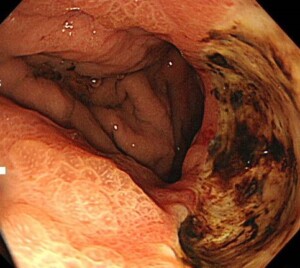

*ロキソニンを数日飲んだだけで出来た胃粘膜障害

*ボルタレン座薬を1か月使用して出来た胃潰瘍(座薬を使用しても粘膜障害、潰瘍のリスクがあります)